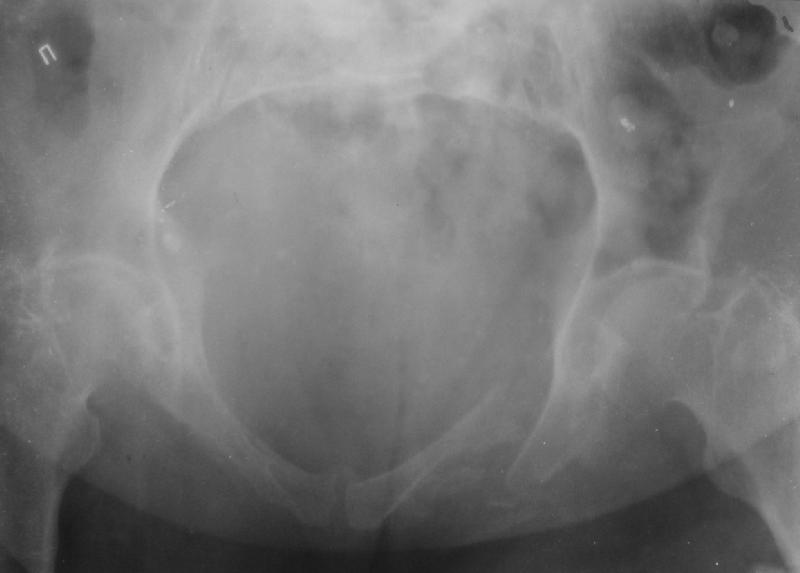

Здравствуйте уважаемые коллеги! Поступила пациентка, 61г, через 1 месяц после травмы, с двусторонним ротационно-нестабильным повреждением тазового кольца: перелом боковых масс крестца с обеих сторон, переломы лонной и седалищной костей слева, отрывные переломы передних остей левой подвздошной кости, сегментарный перелом левой подвздошной кости. Кроме того у пациентки имеется сегментарный перелом левого бедра.

Перелом бедра не вызывает вопросов - планируем блокируемый остеосинтез стержнем, а вот при обсуждении тактики лечения переломов костей таза возник вопрос о необходимости синтеза остей подвздошной кости, учитывая сроки с момента травмы и  наличие остеопороза могут возникнуть технические сложности. Если у кого-нибудь  собственный опыт или ссылки на литературу об отдаленных результатах при не восстановлении сгибательного аппарата бедра?